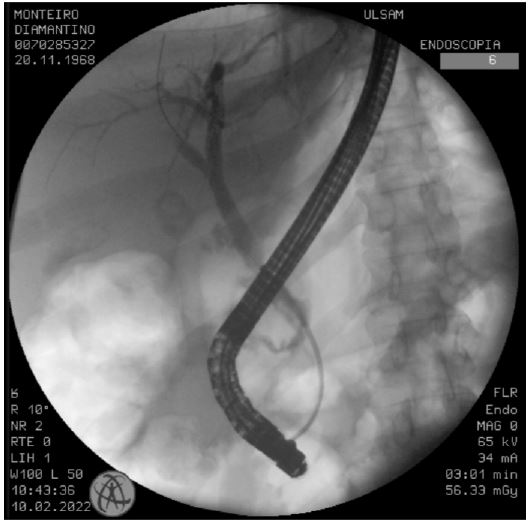

Several days after surgery and once the patient was stabilized, an Endoscopic Retrograde Ccholangiopancreatography (ERCP) was performed. This revealed a high-output bile leak in the distal portion of the main bile duct. The procedure included a sphincterotomy and the placement of a metal bile duct stent (Figure 2).

Figure 2: Image of the ECRP done for treatment of the bile duct leak.